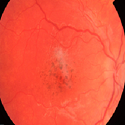

Ataxie spino-cérébelleuse de type 7 (SCA) dignostiqué par l’aspect du fond d’œil

Jaja Zineb, Daoudi Rajae

PAMJ. 2014; 18: 34. Published 09 May 2014